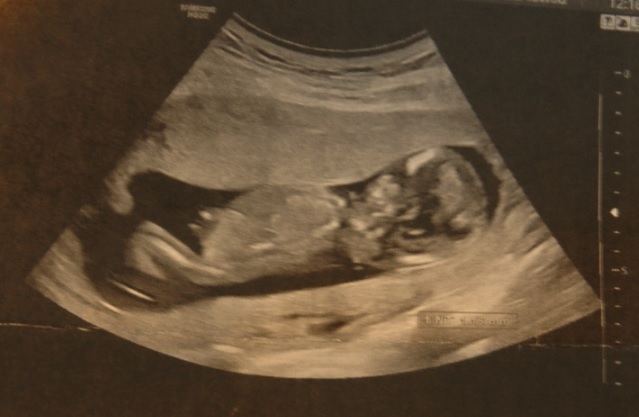

Ám hamarosan ezt a feladatot két pelenkással fogjuk tovább csinálni, mert bejelentkezett hozzánk az Ötödik Gyermek! Azt nem mondom, hogy nem vettünk nagy levegőket, mikor kiderült, és nem gondolkodtunk el azon, hogy miként is fogunk eztán országot járni, kell-e kocsit cserélni, hogyan fogunk beférni (csomagokkal)? Hm… És egyáltalán: HOGYAN FOGJUK MI EZT BÍRNI?